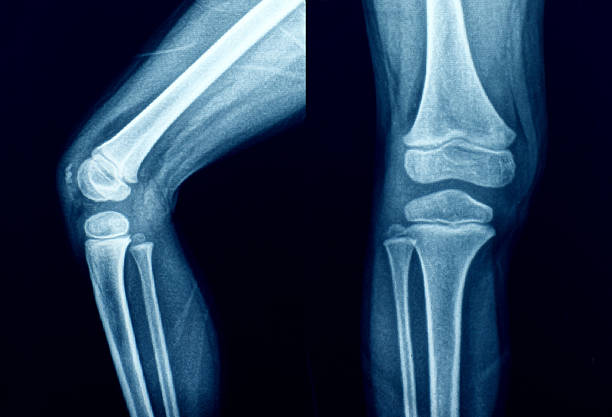

무릎 연골판 손상을 진단하기 위해서는 주로 MRI 검사가 사용됩니다. X-레이 검사는 뼈 위주로 나오기 때문에 연골 손상을 정확하게 확인하기 어렵습니다.